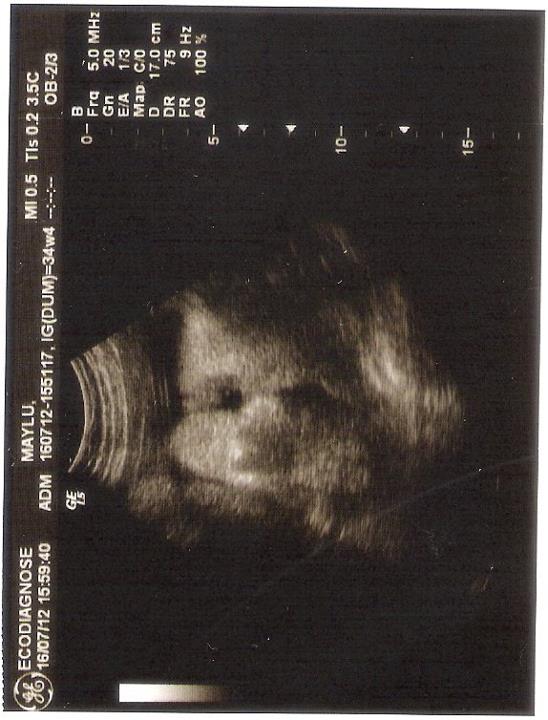

Hoje eu fiz uma US para verificar o Líquido

Amniótico que eu estava perdendo há alguns dias... estou com 34 semanas e 4

dias!

E deu

até para ver o rostinho de Enzo! Ele é bochechudo e cabeludo! Já está cefálico

(encaixadinho de cabeça para baixo) e pesa mais de 2,5 kg!!